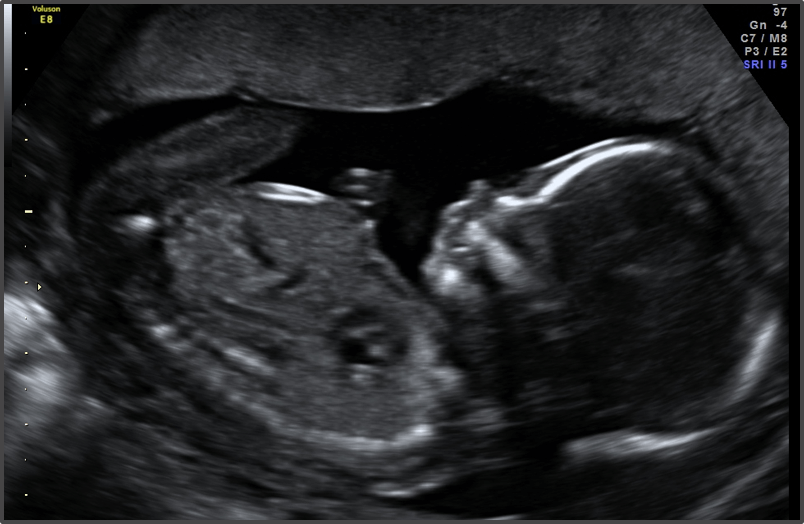

Pregnancy Calculator - Week 16

Baby is the size of Avocado

Approx Baby Weight: 100g

Approx Baby Size: 11.6 cm

Baby Development

Baby’s eyes have formed, and they can sense light.